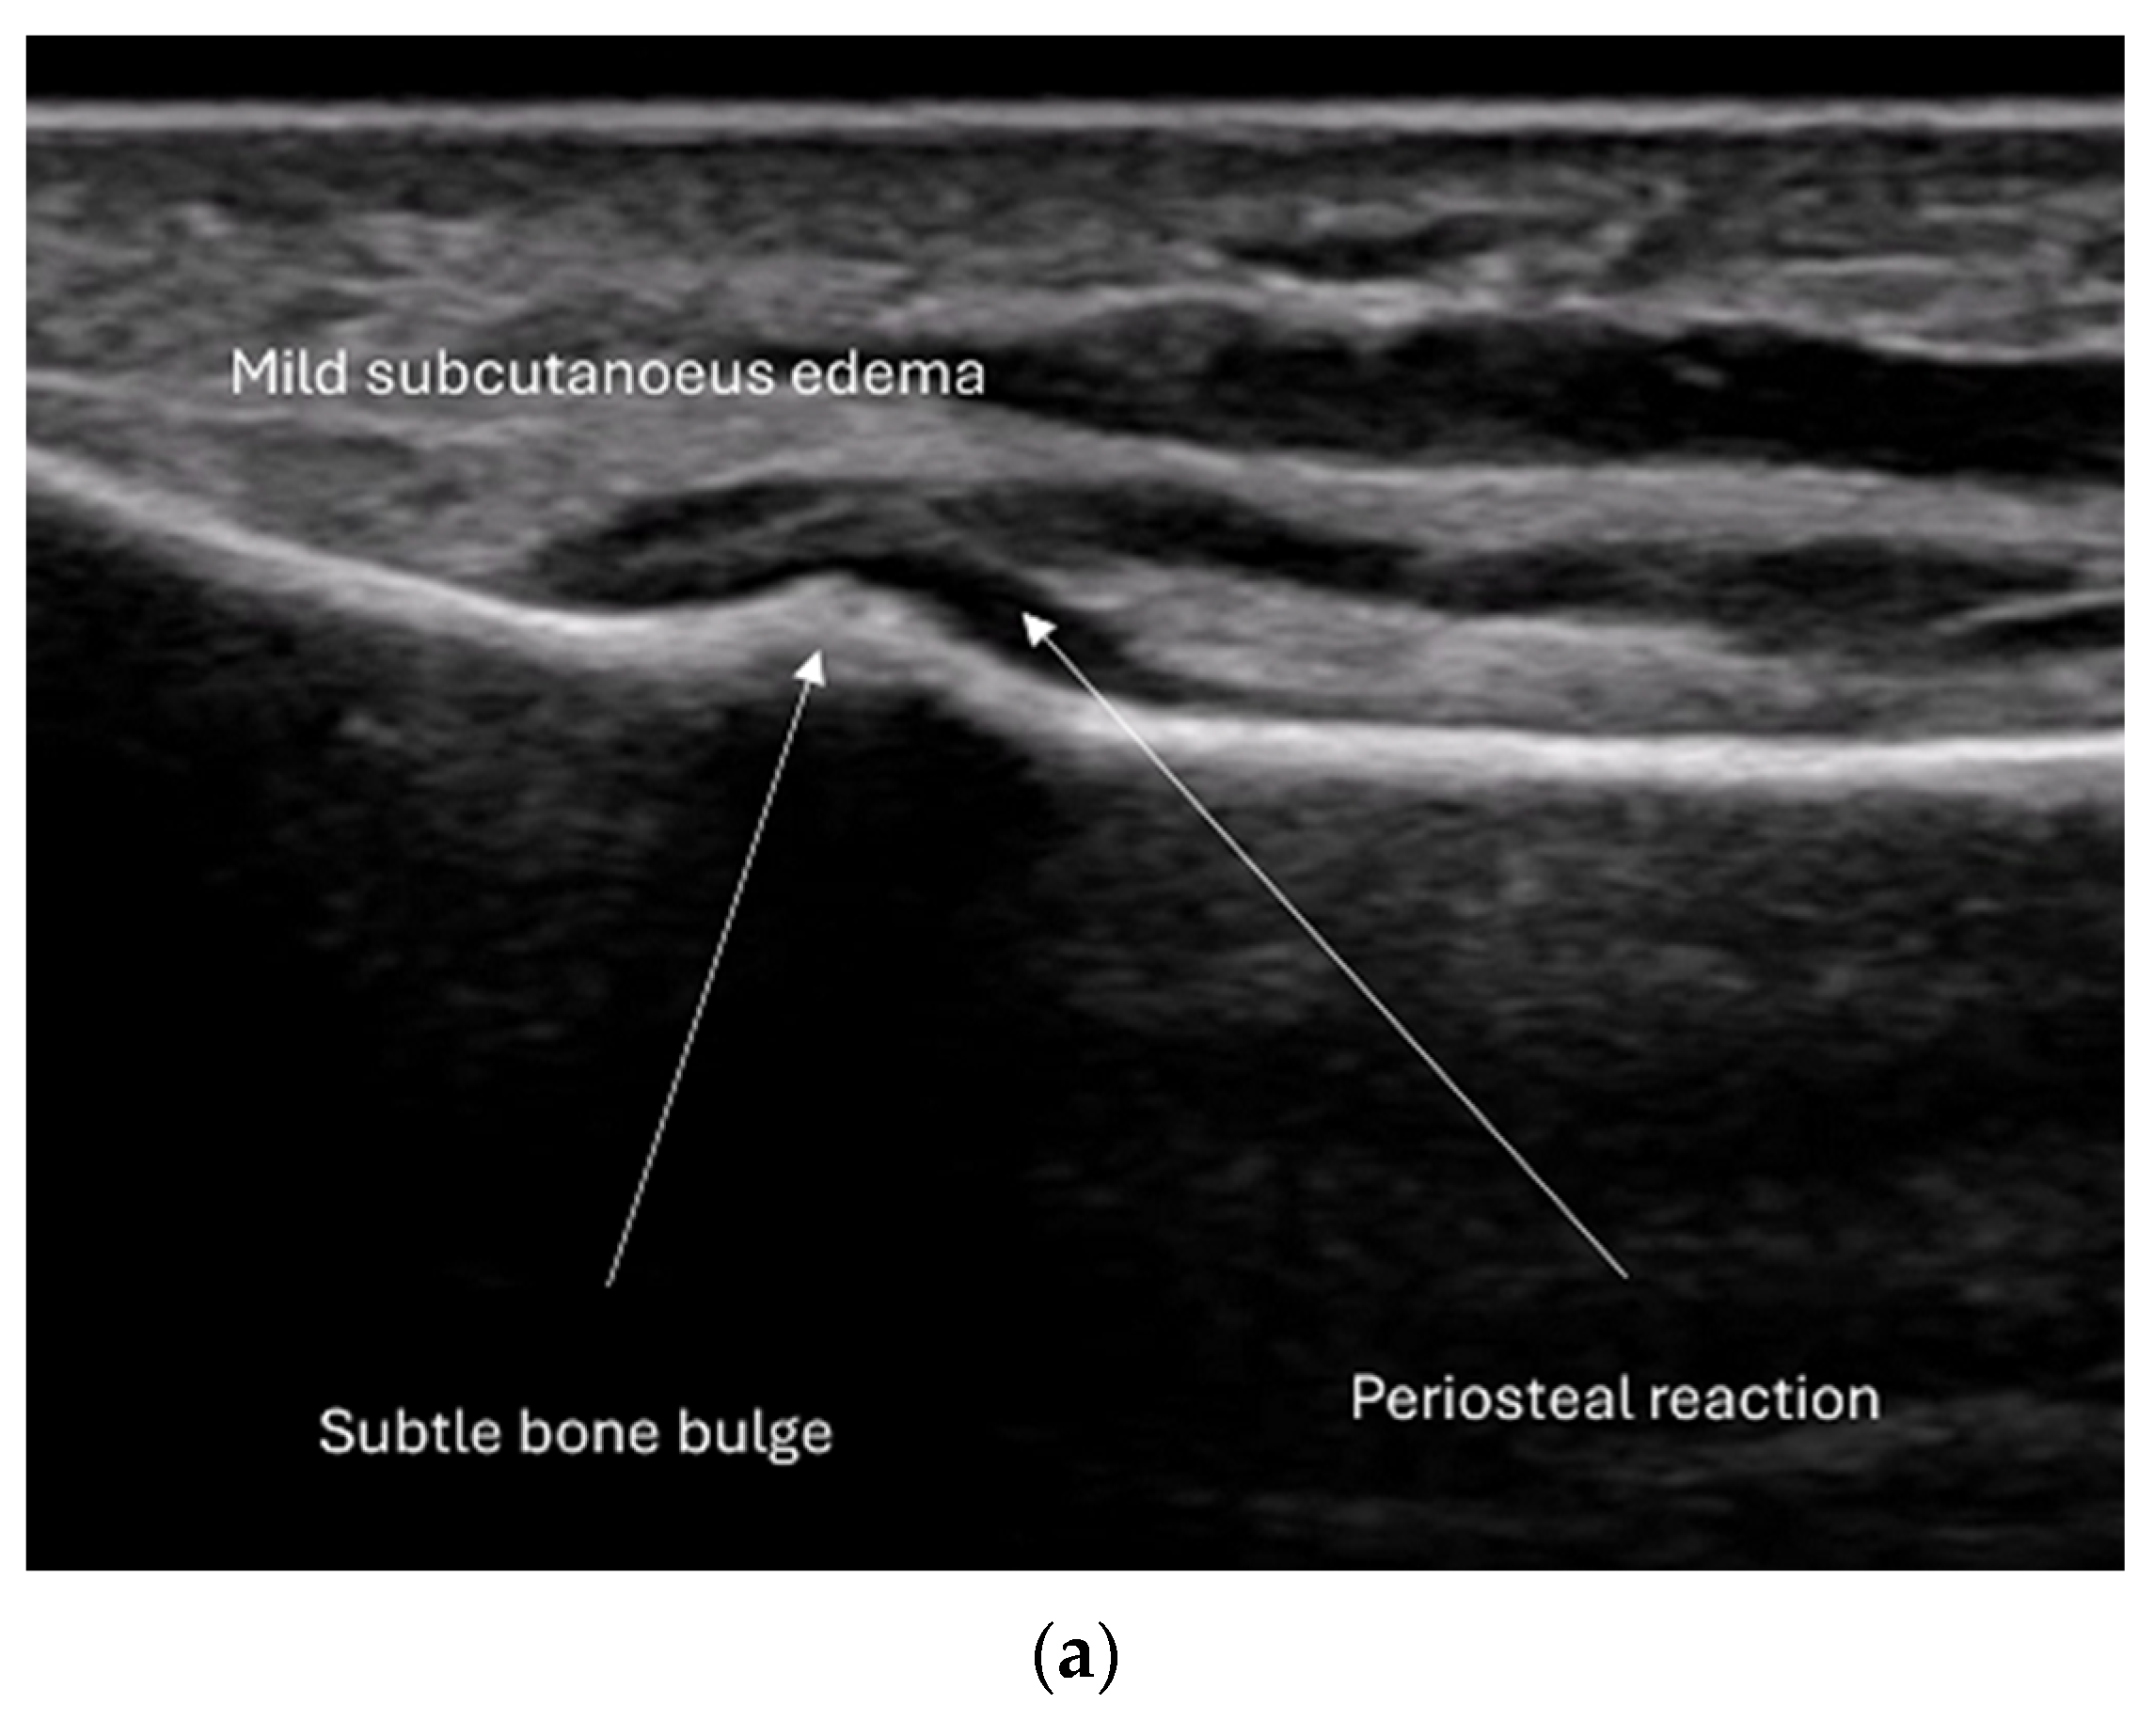

4.2. Sonoanatomy of Fractures [Figure 5, Figure 6, Figure 7 and Figure 8]

- Irregularity, interruption, or gaps in the cortical line: the cortical bone normally appears as a continuous, bright echogenic line, which is interrupted or irregular in the presence of a fracture.

- Bulging or abnormal angulation of the cortical layer: deformities or outpouchings of the normally straight cortical surface indicate displacement or bending at the fracture site.

- Periosteal thickening or elevation: the periosteum may appear thickened or lifted due to injury or early callus formation.